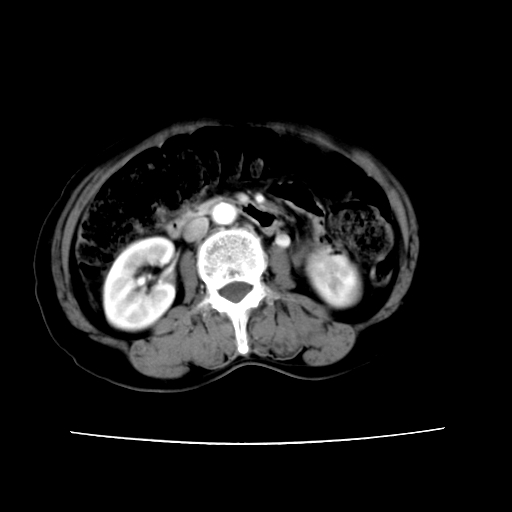

2008-11-10ct平扫(其间去中山医院诊治未行特殊治疗)

2008-11-10ct平扫见并肝内、血膜下血肿基本吸收,肝内低密度灶缩小。此时再做增强ct应有显着意义。对患者/医者都好!

从平扫+增强及治疗后复查片,病变明显缩小,不考虑肝癌出血可能,还是考虑为良性病变可能性大;单纯血肿并包膜下积液吧,病变强化没法解释,肝血管破裂出血吧,增强不符合典型血管瘤的表现,良性肿瘤破裂出血吧,复查片看来好像也不太支持(没做强化也不太好说)。本人还是考虑单纯肝内血肿并包膜下积液,强化是不是血管有外渗。

患者自6月至11月,如果是肝癌,没有经过特殊治疗,想必应该会有所进展吧,而不是ct所见,反而似有病灶减小的趋势。建议增强。

追问病史,患者有过度用力病史,当时立即感腹痛;所以还考虑肝破裂可能性大。